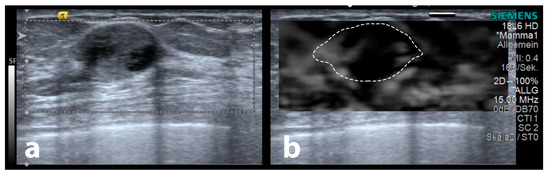

Figure 8.

Sample of an encapsulated papillary carcinoma in the B-mode (a), demonstrating no surrounding strain elastography halo (b). The dashed outline demonstrates the lesion’s B-mode extent.